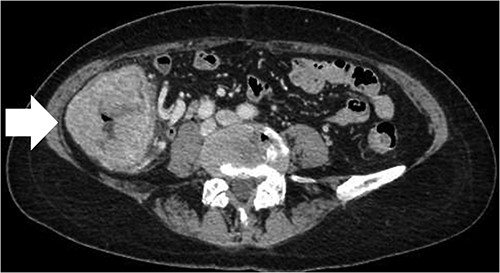

A 68-year-old female patient presented to our hospital with fatigue. She had a history of hypertension and hyperlipidemia. She appeared pale, but a physical examination revealed no other abnormalities. Laboratory findings revealed severe anemia, with a hemoglobin level of 8.8 g/dl. Abdominal computed tomography (CT) revealed tumors in the ascending colon and right lower kidney (Figs 1 and 2). Colonoscopy confirmed a Type 1 tumor in the ascending colon, and biopsies of this lesion revealed papillary adenocarcinoma. Preoperative TNM classification according to UICC classification was colon cancer, stage cT3N0M0, and right renal cancer, stage cT1aN0M0. Because both lesions were indications for robotic surgery, the patient underwent synchronous robotic right hemicolectomy and right partial nephrectomy using the robot da Vinci® Xi. Following the induction of general anesthesia, the patient was placed in the supine position. The first 8-mm trocar was inserted through the umbilicus using the Hasson method. The pneumoperitoneal pressure was maintained at 12 mmHg. Additionally, three 8-mm trocars were inserted under laparoscopic vision in the right lower abdomen, left lower abdomen and upper left abdomen, and a 12-mm trocar for assistance was inserted in the left abdomen (Fig. 3). The table was rotated slightly to the left and 10° head down. The robot was rolled in from the patient’s right side and docked. Robotic Arm 1 was affixed with bipolar forceps, Arm 2 had monopolar scissors and Arm 3 had a cadiere forceps. Starting with the inferior approach, the right ureter, gonadal vessels and Gerota’s fascia were preserved. The duodenum and pancreatic head were spared on the dorsal side, and the mesentery was mobilized.

CT scan of the renal tumor in the lower pole of the right kidney (arrow).